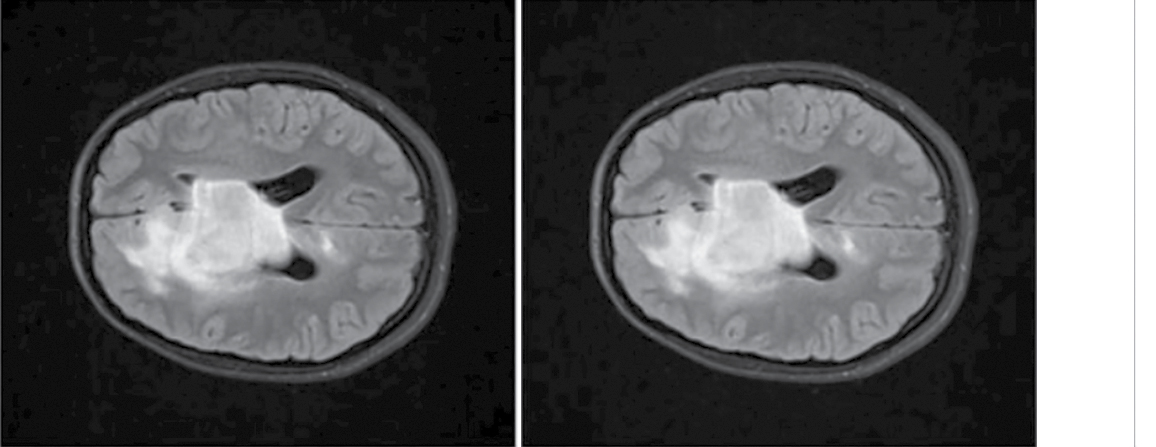

At the previous study stage, we found that the majority of the radiomic predictors characterize ROI heterogeneity by gray level intensity of the voxels. Hence, the higher performance of the model built using the method of the current study stage can be associated with the contrast adjustment. Gamma (γ) value adjusts the contrast as a function: γ < 1 reduces contrast, and γ > 1 augments contrast. At the current study stage, γ was > 0.9, which means that the image contrast was slightly reduced (Fig. 5).

Fig. 5. Diffuse glioma (Т2-FLAIR, ах).

A — raw data; B — AdjustContrast transformed (γ = 0.9).

Let us compare these image preprocessing techniques. The ScaleIntensity transform is meant to uniformly increase the brightness of an image by adjusting the values of all its voxels. As a rule, the voxel values are scaled to the predefined value range by applying the linear transformation. For example, the ScaleIntensity transform can scale voxel values, which were initially in the range of 0–255, to a predefined range, often improving the quality of image interpretation without significant change of voxel-to-voxel ratio. In other words, ScaleIntensity allows us to augment the brightness of the image, preserving the texture of dark and light areas (Fig. 6). Uniform adjustment mitigates the risk of information loss due to critically excessive voxel intensity values.

Fig. 6. Diffuse glioma (Т2-FLAIR, ах).

А — raw data; В — ScaleIntensity transformed data.